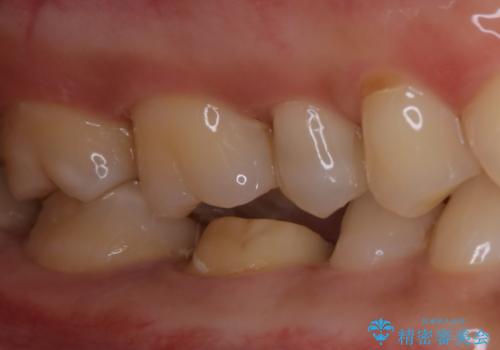

- 銀歯のやり替えをご希望された患者様です。手前の歯にもプラスチックと歯の間に虫歯が出来ていたため、両方とも適合の良いセラミックで補綴しました。

- セラミックインレー7.7万円・仮歯1.1万円・フルジルコニアクラウン7.7万円(税込)費用は治療当時の料金となります